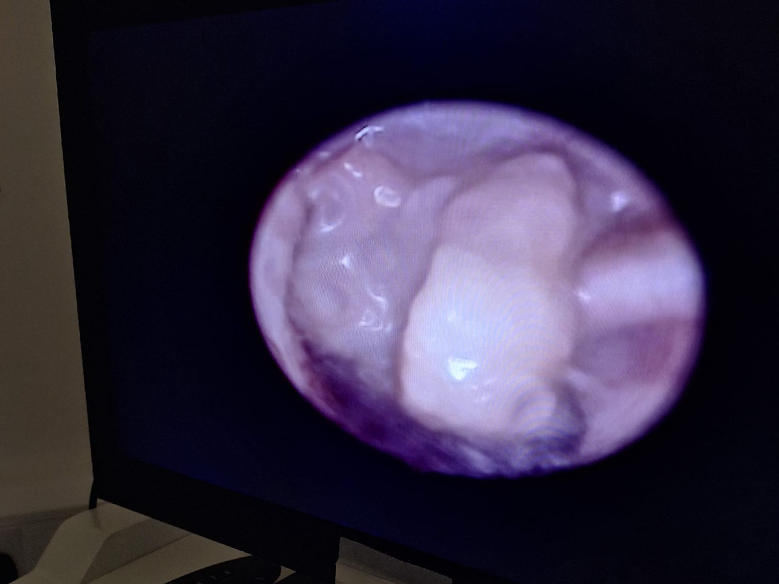

Ear Disease and Video-Otoscopy

Chronic ear disease in dogs, commonly known as chronic otitis, is a long-lasting condition that affects the ear canal. It can stem from a variety of underlying issues, such as allergies, infections, or structural abnormalities. This condition often requires ongoing management and may persist due to incomplete or ineffective treatment, or a failure to identify the root cause.

To enhance treatment, we frequently use a video otoscope, which offers outstanding clarity for evaluating the ear canal, eardrum, and sometimes the middle ear. This procedure typically necessitates anaesthesia because of the delicate nature of the ear and the need for the patient to remain completely still. In many instances, this examination is needed only once, while some cases may require multiple assessments to effectively address specific infections or complex conditions.